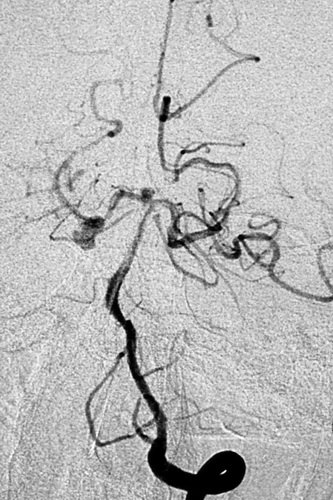

全脑血管造影提示:左侧颈内动脉主干血管明显狭窄,大脑中动脉及前动脉基本闭塞,左侧供血差,颈外动脉有少量代偿,左侧椎动脉造影示右侧大脑后动脉P2段夹层、基底动脉顶端,分别大小为6 mmX5mmX4mm瘤颈约5mm;4 mmX4mmX3mm瘤颈约3mm。

左侧椎动脉2D造影示右侧大脑后、基底动脉顶端动脉瘤